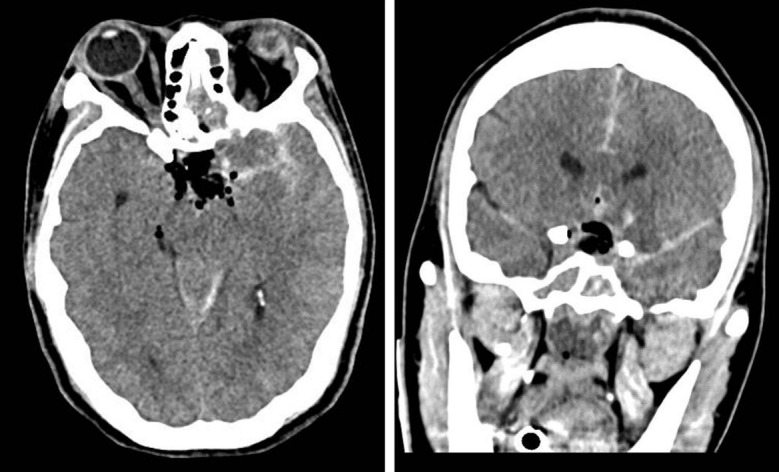

垂体手术后脑缺血并发症的报道并不多见。多种机制被提出,包括术后蛛网膜下腔出血引起的血管痉挛和延迟性脑缺血。鉴于这些情况下血管痉挛的病因不明,对其预防知之甚少。通过一份病例报告和文献回顾,作者警告术后识别可能表明脑血管痉挛风险增加的关键体征的重要性,必须及时识别,一旦出现这些症状就采取适当的治疗策略。

Cerebral ischemic complications after pituitary surgery are not frequently reported. Multiple mechanisms have been proposed, including vasospasm, and delayed cerebral ischemia resulting from postoperative subarachnoid bleeding. Given the unknown etiology of vasospasm following these situations, little is known about its prevention. Through a case report and bibliographic review, the authors warn about the importance of recognizing key signs postoperatively that could indicate increased risk for cerebral vasospasm and must be recognized in a timely manner, with appropriate treatment strategies implemented once these symptoms present.